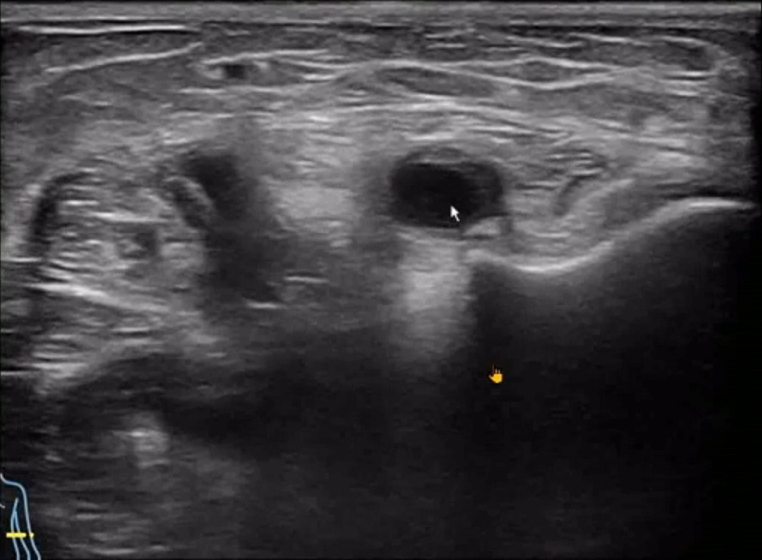

The ultrasound revealed carpal tunnel syndrome with synovial cysts compressing the recurrent motor branch of the median nerve.

For medical professionals looking to buy a handheld ultrasound machine, this case highlights the machine' s ability to detect subtle post-surgical complications that could otherwise be missed.